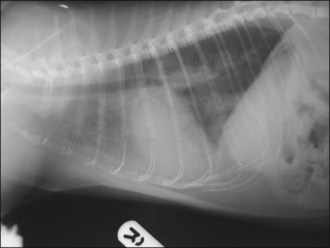

One hour later the dog’s respiration had improved to some extent and he had also urinated. As he was compliant, thoracic radiographs were performed with flow-by oxygen supplementation throughout (Figure 31.1). These findings were consistent with the suspected diagnosis of decompensated left-sided CHF secondary to probable mitral valve insufficiency but there was also evidence of right-sided heart failure.

Figure 31.1 (a) Right lateral and (b) dorsoventral thoracic radiographs of a dog with end-stage mitral valve disease showing cardiomegaly with left atrial enlargement and dorsal displacement of the caudal part of the trachea, an alveolar lung pattern affecting mainly the cranial lung lobes with air bronchograms, mild bilateral pleural effusion and hepatomegaly.